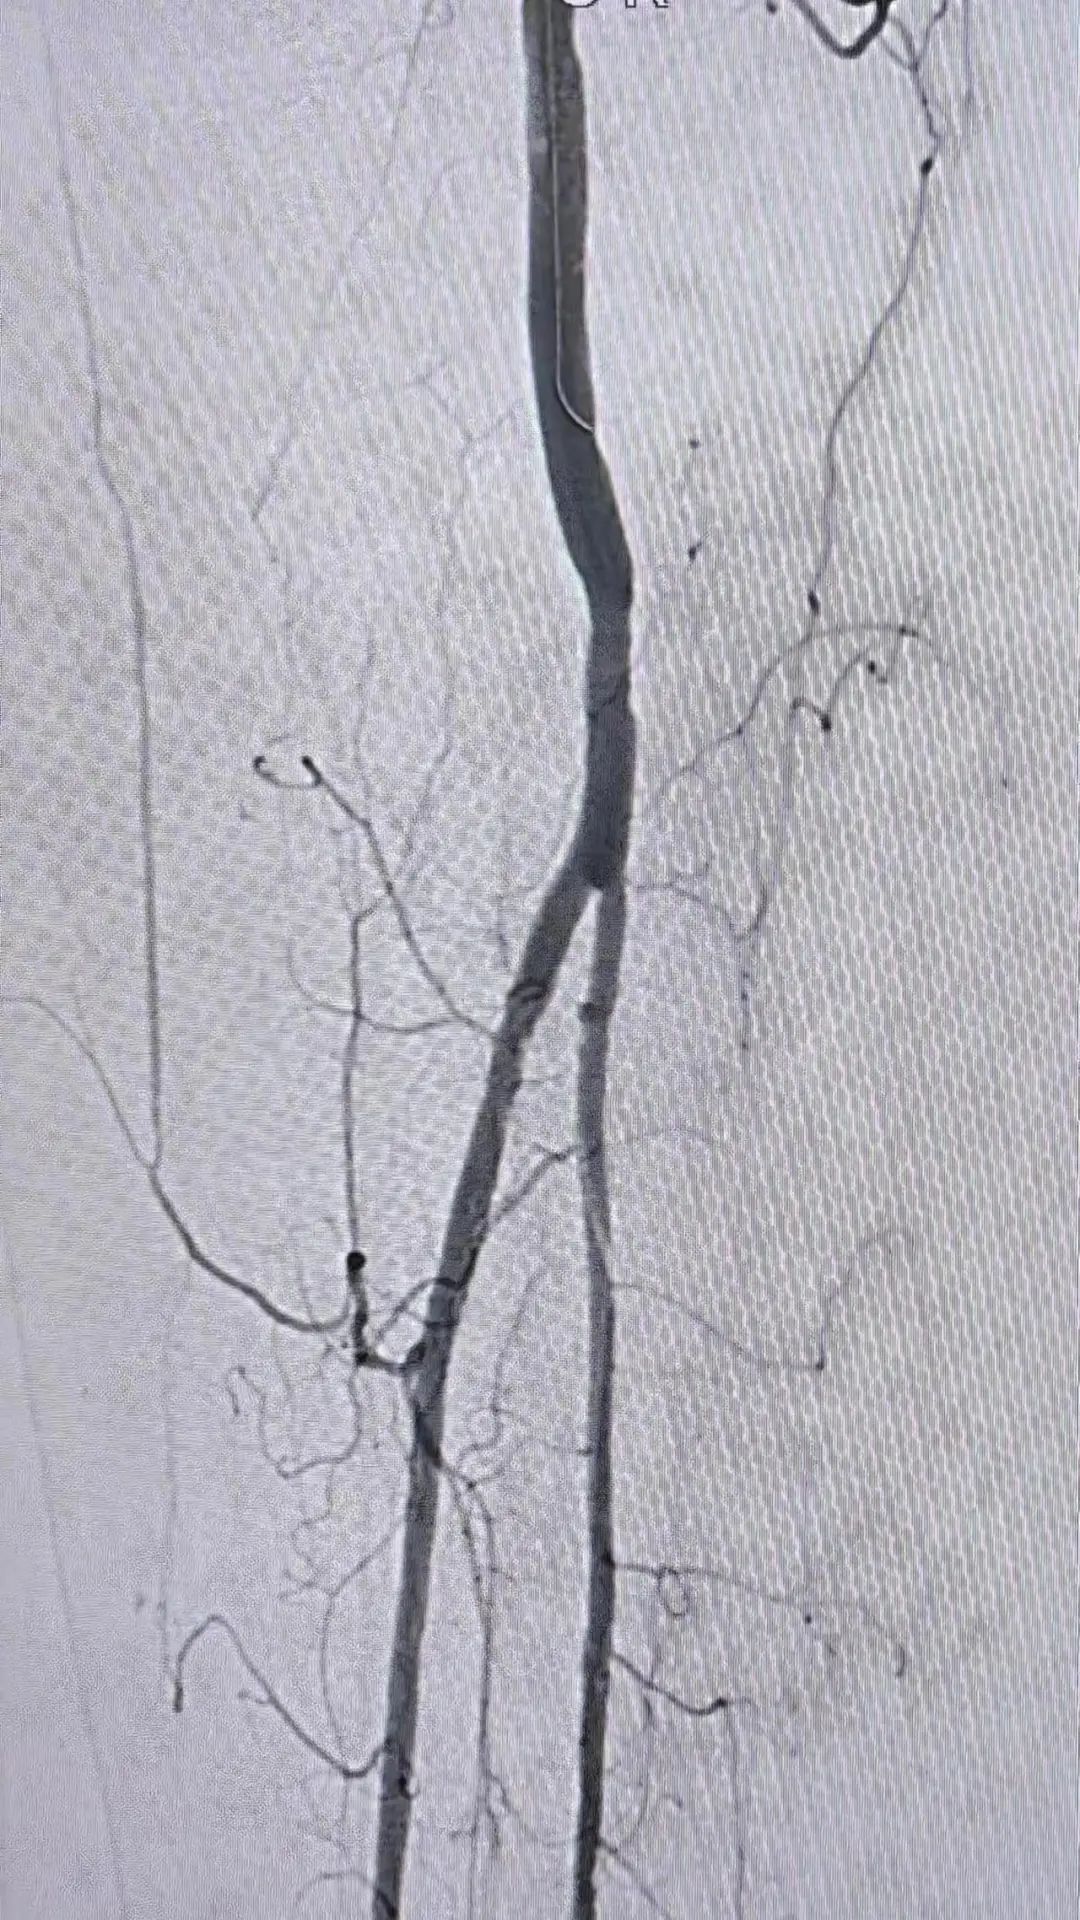

3.溶栓+球囊成形术后造影:

图片

患肢动脉血栓清除,无明显残留狭窄,血流流速良好,足底动脉弓显影良好。